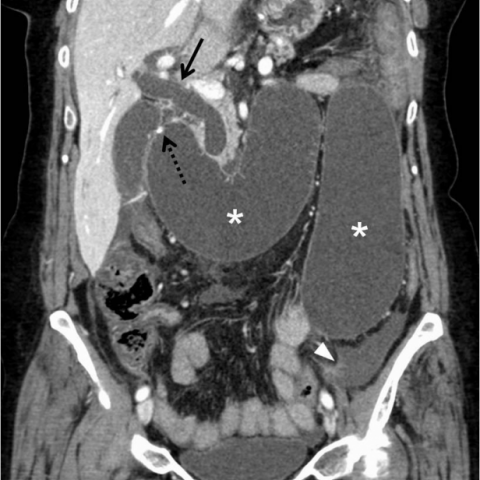

52세 남성이 10일 전에 위암으로 위 하부 절제 수술을 받았다. 수술 후 복통과 간헐적인 담즙성 구토를 호소한다. 통증은 지속적이며, 구토 후에 일시적으로 완화된다. 복부 CT 사진이다. 진단은?

위절제술 후 담즙성 구토와 복통을 보이는 환자이다. CT상 담도확장(→) 및 담즙/췌액 저류로 인해 distention된 afferent loop(*) 이 관찰되므로 afferent loop syndrome 으로 진단할 수 있다.